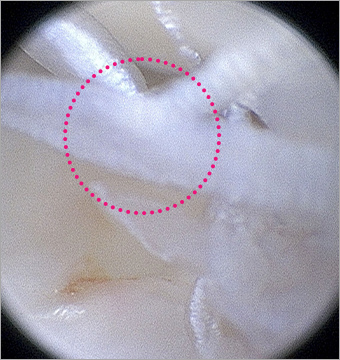

관절경을 이용한 수술

관절경을 이용한 수술은 최소 통증, 빠른 회복이 큰 장점으로 근육・힘줄을 최대한 보존하는 최소 침습 수술 시행합니다.

단열된 십자인대

단열된 십자인대

정상 반월판의 물결 모양

(Oyster flounce)

본원 시술 사진